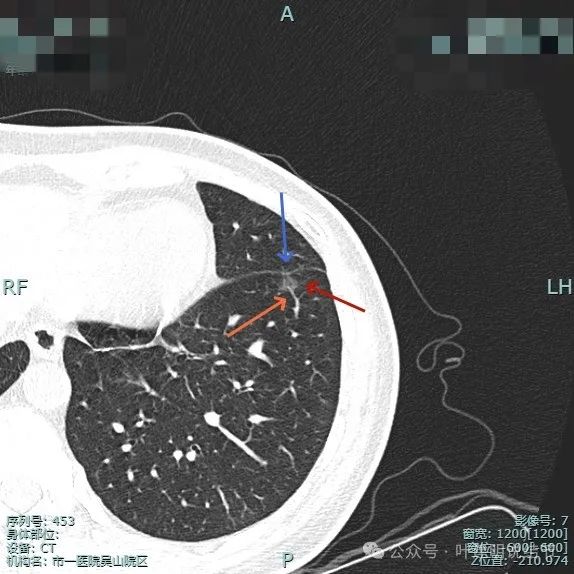

他处也有小血管进入,整体轮廓与边界清。

边缘显得毛糙。

边缘区也是磨玻璃密度。